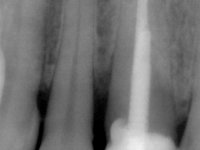

Female patient, 41 years old, non-smoker. It presented tooth 11 with a composite resin restoration, of great extension, very infiltrated and aesthetically poor. In the imaging exam, it was verified that the endodontic treatment was not technically satisfactory, but asymptomatic for almost 20 years. Between teeth 11 and 12 it showed a periodontal pocket certainly related to the non-adapted restoration. Tooth 11 showed a reduced mesiodistal diameter in relation to the symmetrical one. Medium thickness periodontal with satisfactory oral hygiene.

It was proposed to the patient to make a full-coated crown with a ceramic-coated Zr infrastructure that would aesthetically and functionally rehabilitate tooth 11. We decided not to redo the endodontic treatment given the absence of signs and symptoms for more than 20 years. The coronary structure would be previously reinforced with the placement of an intraradicular post and the making of a new restoration in composite resin. Periodontal pocket would be surgically addressed.